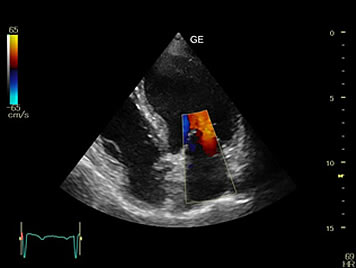

Our professionals at EWH are trained to use state of the art ultrasound technology to provide ultrasound diagnoses